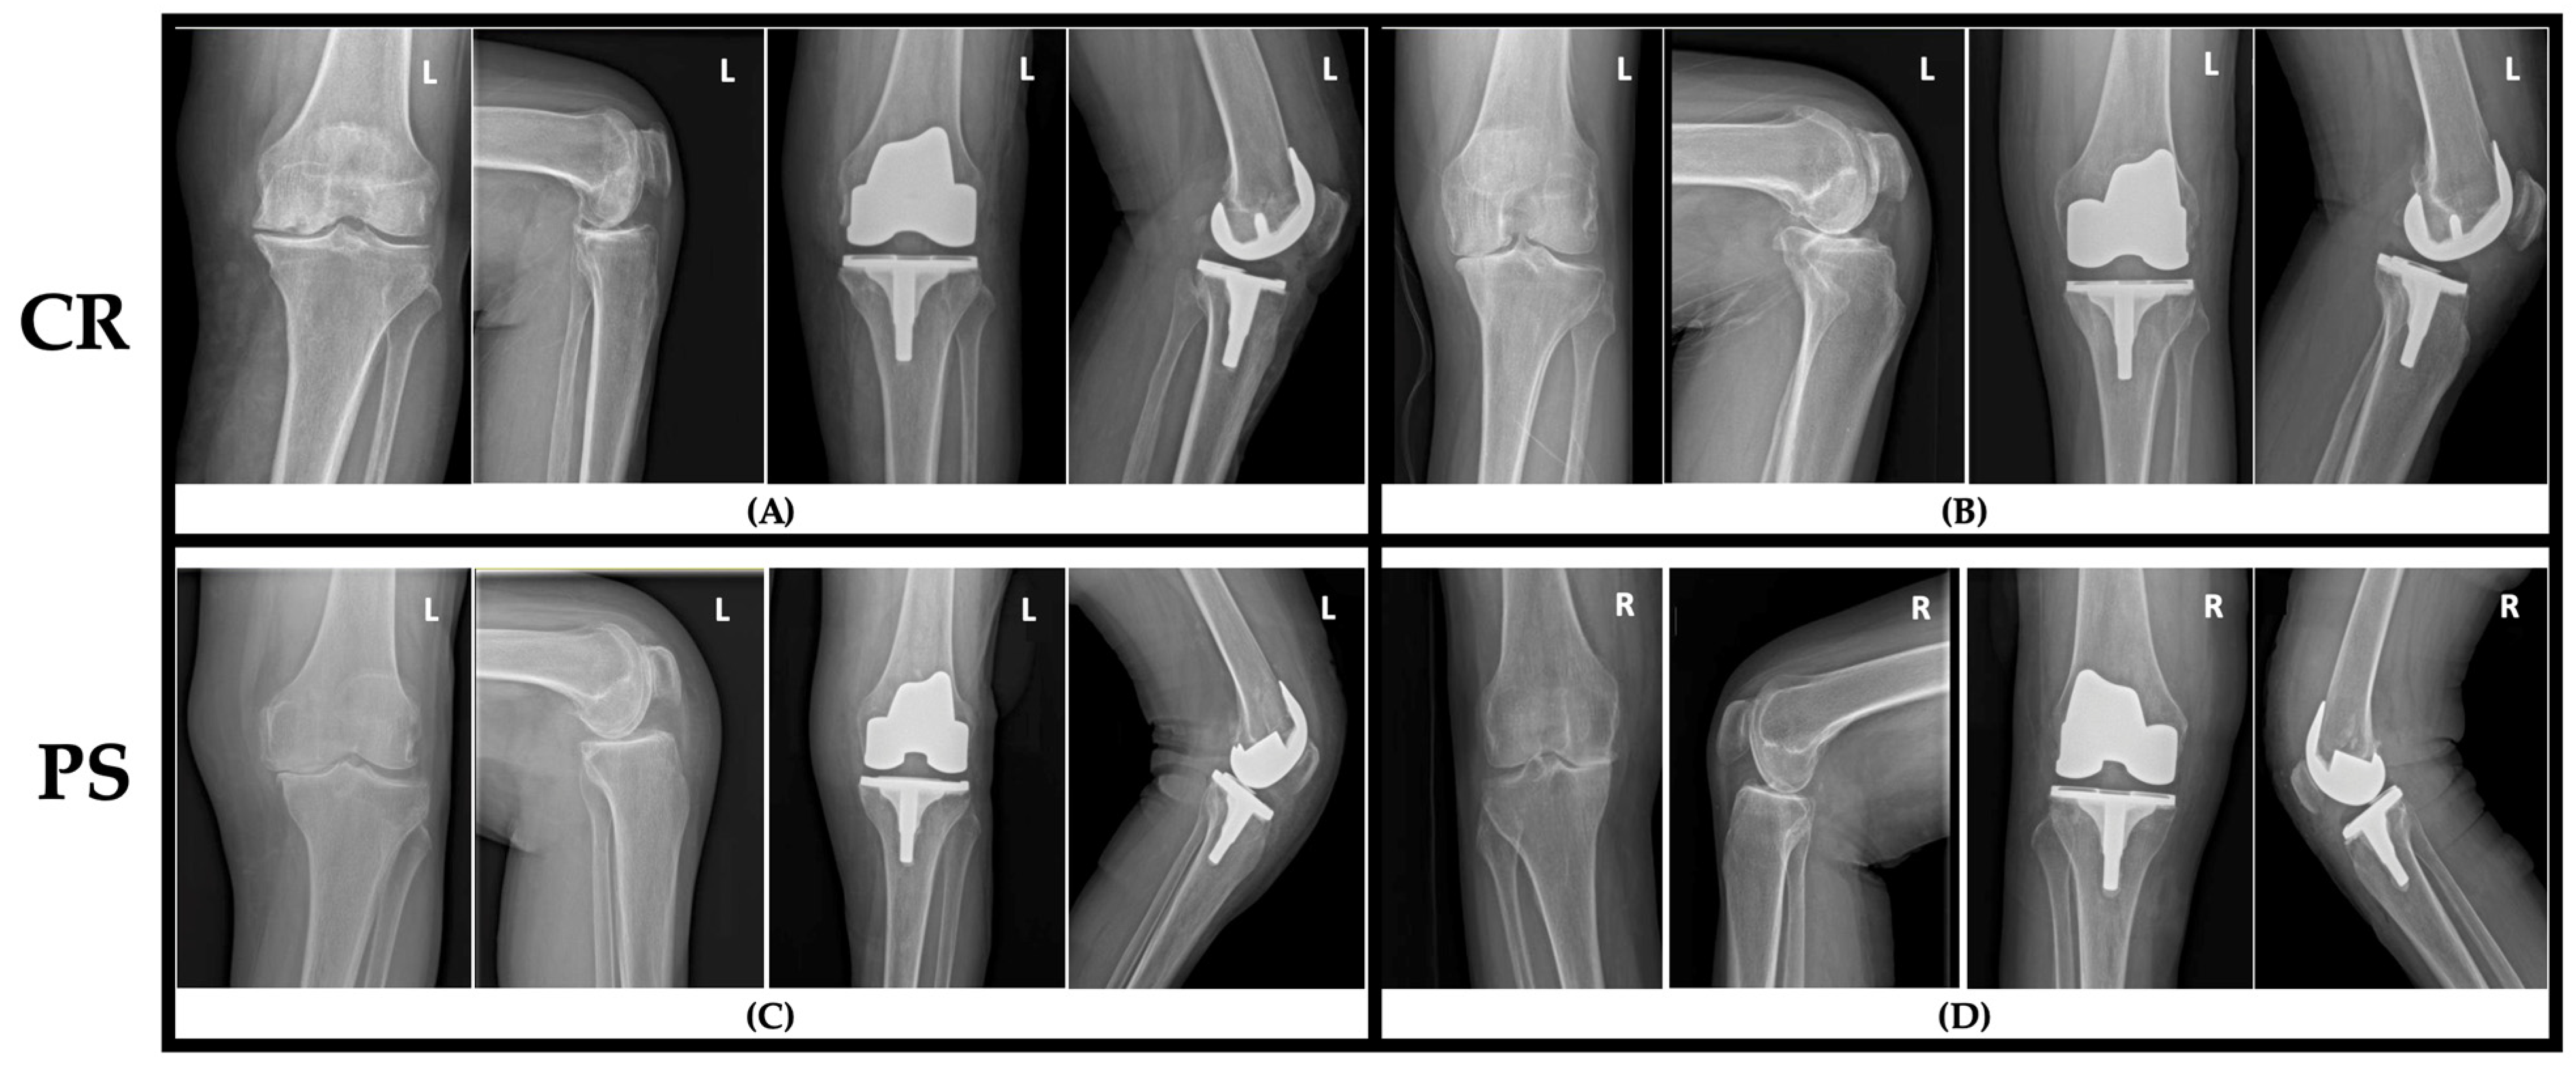

2.3. Implant Selection

2.4. Surgical Procedure